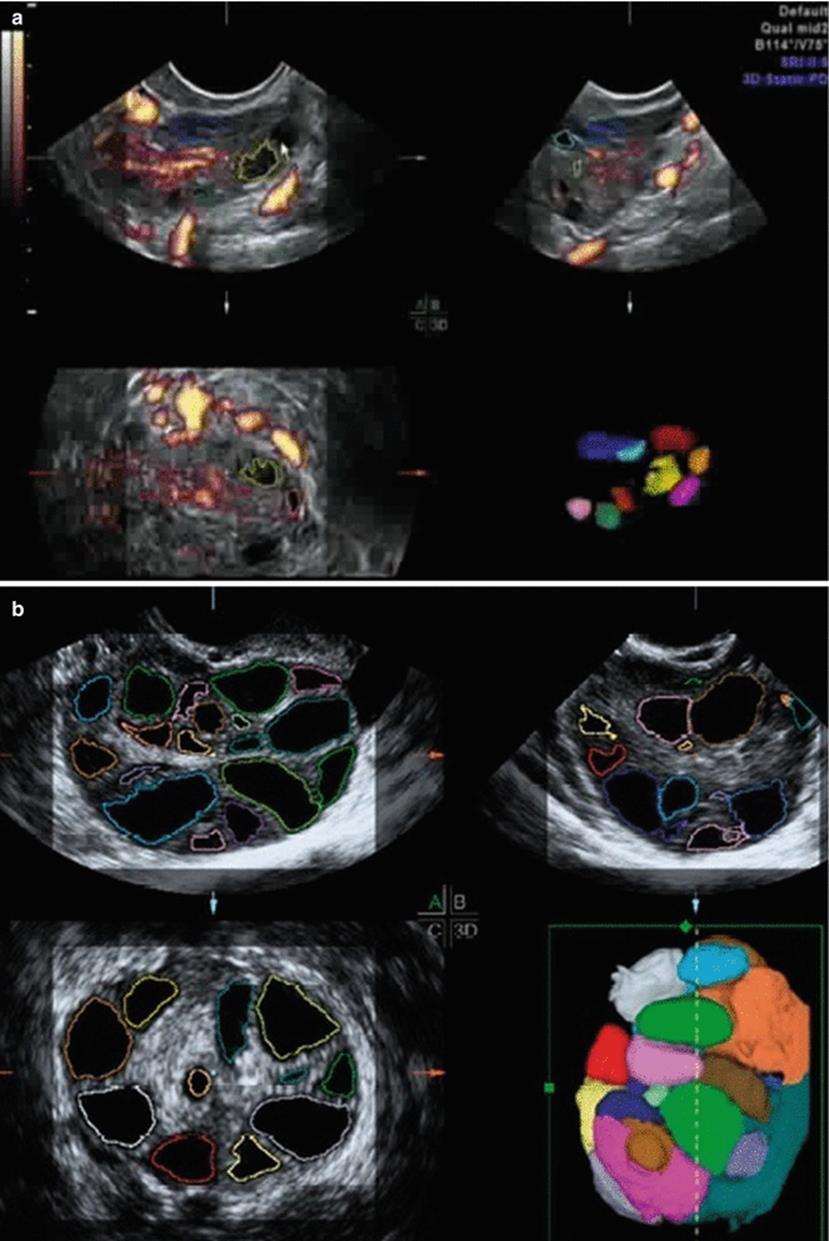

Tridimensional Automated USG for Monitoring Controlled Ovarian Stimulation Cycles

Two-dimensional USG is difficult and less reliable in the presence of numerous follicles of different sizes during COS and is also relatively arbitrary. Accurate assessment of follicular size is required for timing and oocyte collection as significantly less mature oocytes are recovered from follicles with a mean diameter of <15 mm. Three-dimensional ultrasonography-based automated volume count (SonoAVC) can individually identify and quantify the size of any hypoechoic region within the 3D data sets (Fig. 2.26), providing an automatic estimation of their absolute dimension and volume. It estimates the volume of follicle to within ±0.5 cm3. This enables the quantification of an unlimited number of volumes that arise in a COS cycle, as it eliminates the possibility of measuring the same follicle more than once. Thus, Sono AVC is a quicker and more reliable method of measuring follicles in a COS cycle, but its effect on the pregnancy rate has not yet been studied. The number of the mature oocytes, fertilized oocytes, and clinical the pregnancy rates (42 % vs. 43 %) were similar with both 2D ultrasound and Sono AVC methods [49].

Fig. 2.26

(a, b) SonoAVC for follicular monitoring

Three-dimensional ultrasound with Sono AVC significantly improves the interobserver reliability of antral follicle counts and allows quicker assessment of follicle size and number, making it an important tool in the assessment of ovarian reserve.

It however, has the following disadvantages:

· Increases time of ultrasound as a lot of time may be spent postprocessing.

· If two or three follicles are close by, it measures them as one, and it is the operator who needs to identify and separately count these follicles using the snipping tools.

· At times, certain follicles may not be measured at all and the operator needs to scan the ovary in X-, Y-, and Z-axis to identify the left out follicles.

· The clinical outcome of assisted reproduction treatment also did not show any improvement with the use of SonoAVC, and so we need to determine whether it is cost-effective to be used routinely in all IVF cycles [50].